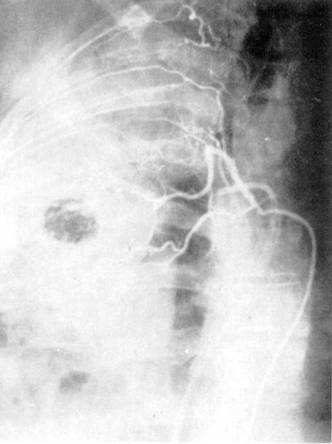

Ангиопульмонография — способ контрастного исследования сосудов малого круга кровообращения. Чаще всего показания к ангиопульмонографии определяются как дифференциально-диагностические: при пороках развития легкого, нагноительных заболеваниях, бластоматозном процессе. Она дает также возможность определить функциональное состояние паренхимы легкого, оценить гемодинамику Различают четыре способа ангиопульмонографии: 1) общую ангиопульмонографию, выполняемую путем внутривенного введения контрастного вещества или посредством ангиокардиографии из правого желудочка сердца; 2) селективную ангиопульмонографию, выполняемую из ствола или ветвей легочной артерии; 3) суперселективную ангиопульмонографию, включающую контрастирование из долевых, сегментарных ветвей легочной артерии; 4) окклюзионную ангиопульмонографию, выполняемую при заклинивании субсегментарной или лобулярной ветви легочной артерии концевой частью сердечного катетера или при блокировании баллоном катетера магистральной ветви легочной артерии. Ангиопульмонография производится в рентгенооперационных, обеспечивающих телевизионный рентгенологический и физиологический контроль, оснащенных автоматическими инъекторами для быстрого, дистанционного и синхронного с рентгенографией введения контрастного вещества (уротраст, верографин и др.) в сосуды и сердце. Сердечный катетер вводится в сосуды, как правило, чрескожно-чрезбедренным способом.

Рис. 6. Ангиопульмонография.

Рис. 7. Селективная ангиография бронхиальных артерий.

Контрастное исследование сосудов средостения включает в себя флебографию и аортографию. Флебография выполняется с учетом характера патологического процесса, выявляемого при помощи рентгенографии, томографии, бронхографии. При указании на вероятное поражение лимфатических узлов переднего средостения выполняют верхнюю кавографию и контрастное исследование внутренних грудных вен, а при подозрении на поражение лимфатических узлов заднего средостения — азигографию. При анализе ангиопульмонограмм обращают внимание на пофазовое продвижение контрастного вещества по различным регионам легкого: легочной артерии, капиллярного русла, венозной системы малого круга кровообращения (рис. 6).

По комбинации ангиографических признаков представляется возможным охарактеризовать вид и распространенность патологического процесса (при двухпроекционной сериографии — посегментарно) в легком, при этом обращается внимание на наличие деформации сосудов, смещение, контуры, разреженность сосудистого рисунка (рарефикацию), степень развития сосудов отдельных сегментов, долей, легкого, характер расположения камер сердца, ротацию сердца и др.